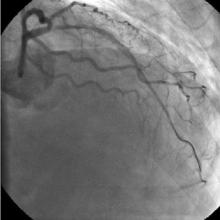

3) LAD: Ostial CTO ( Figure 2) with collaterals from RCA and LCX (Figure 3).